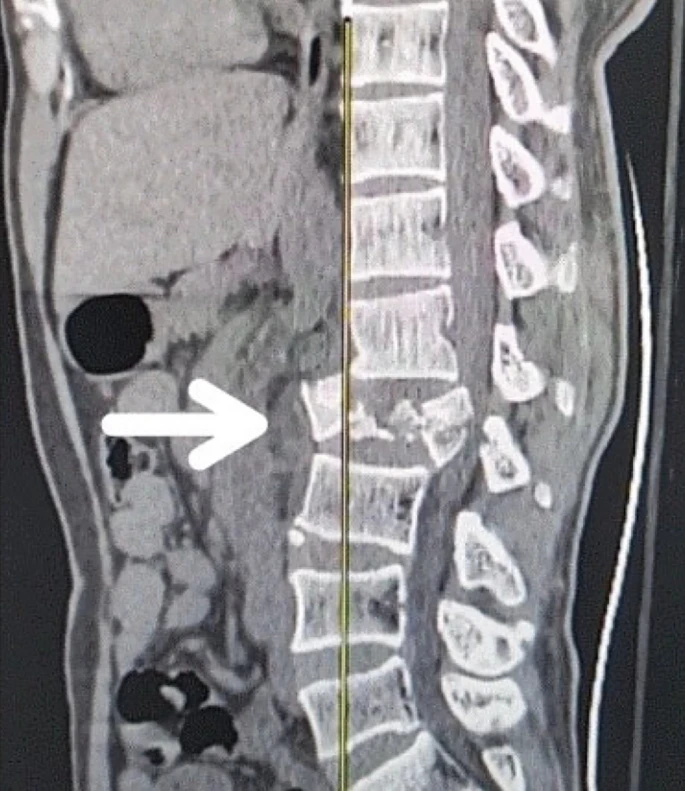

創傷性脊髓損傷是由于脊柱受到突然的強力撞擊,導致椎骨骨折、脫臼、擠壓或壓縮(圖1)。主要原因包括機動車事故,其中汽車和摩托車碰撞占每年新增脊髓損傷病例的近一半。跌倒,尤其是65歲及以上人群的跌倒,是造成脊髓損傷的重要原因,約占60%。體育活動,例如沖擊性運動和淺水潛水,約占此類損傷的10%。

慢性期開始于損傷后約3-6個月,并持續患者的余生,典型特征是囊腫形成和嚴重的神經膠質瘢痕(圖2)。